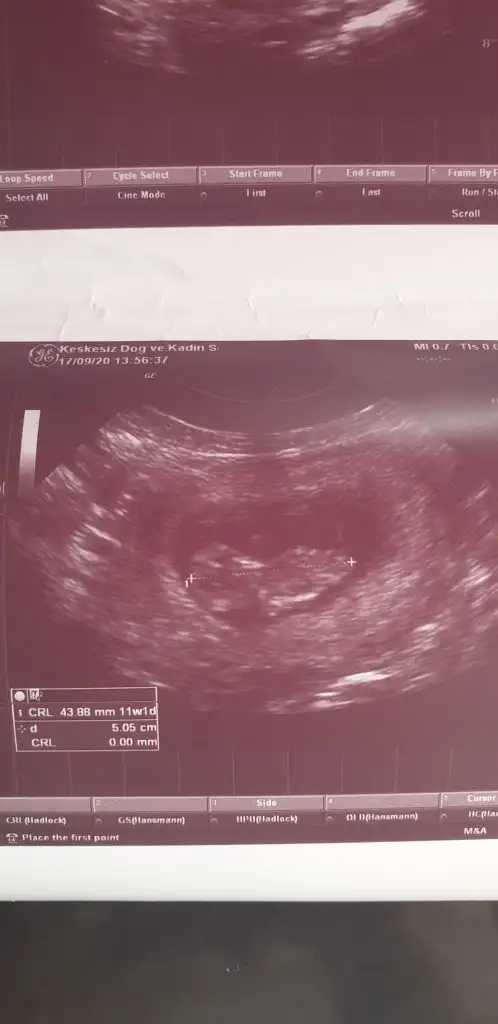

Yine hic net degil doktor.gordum dedi ama yorum mersk ediyorum doktor yuzdede vermedi netde demedi ama bilemedim belki bisiyler dersin son kez cnm bikac kezde atmıştım doktor yine ultrason goruntusu vermedi net goruntu yakalayamadi diye ben ekrani cektim Ikra meyra Ikra meyra 13+4

Nub iyi gozukmoyor ama sanki erkek